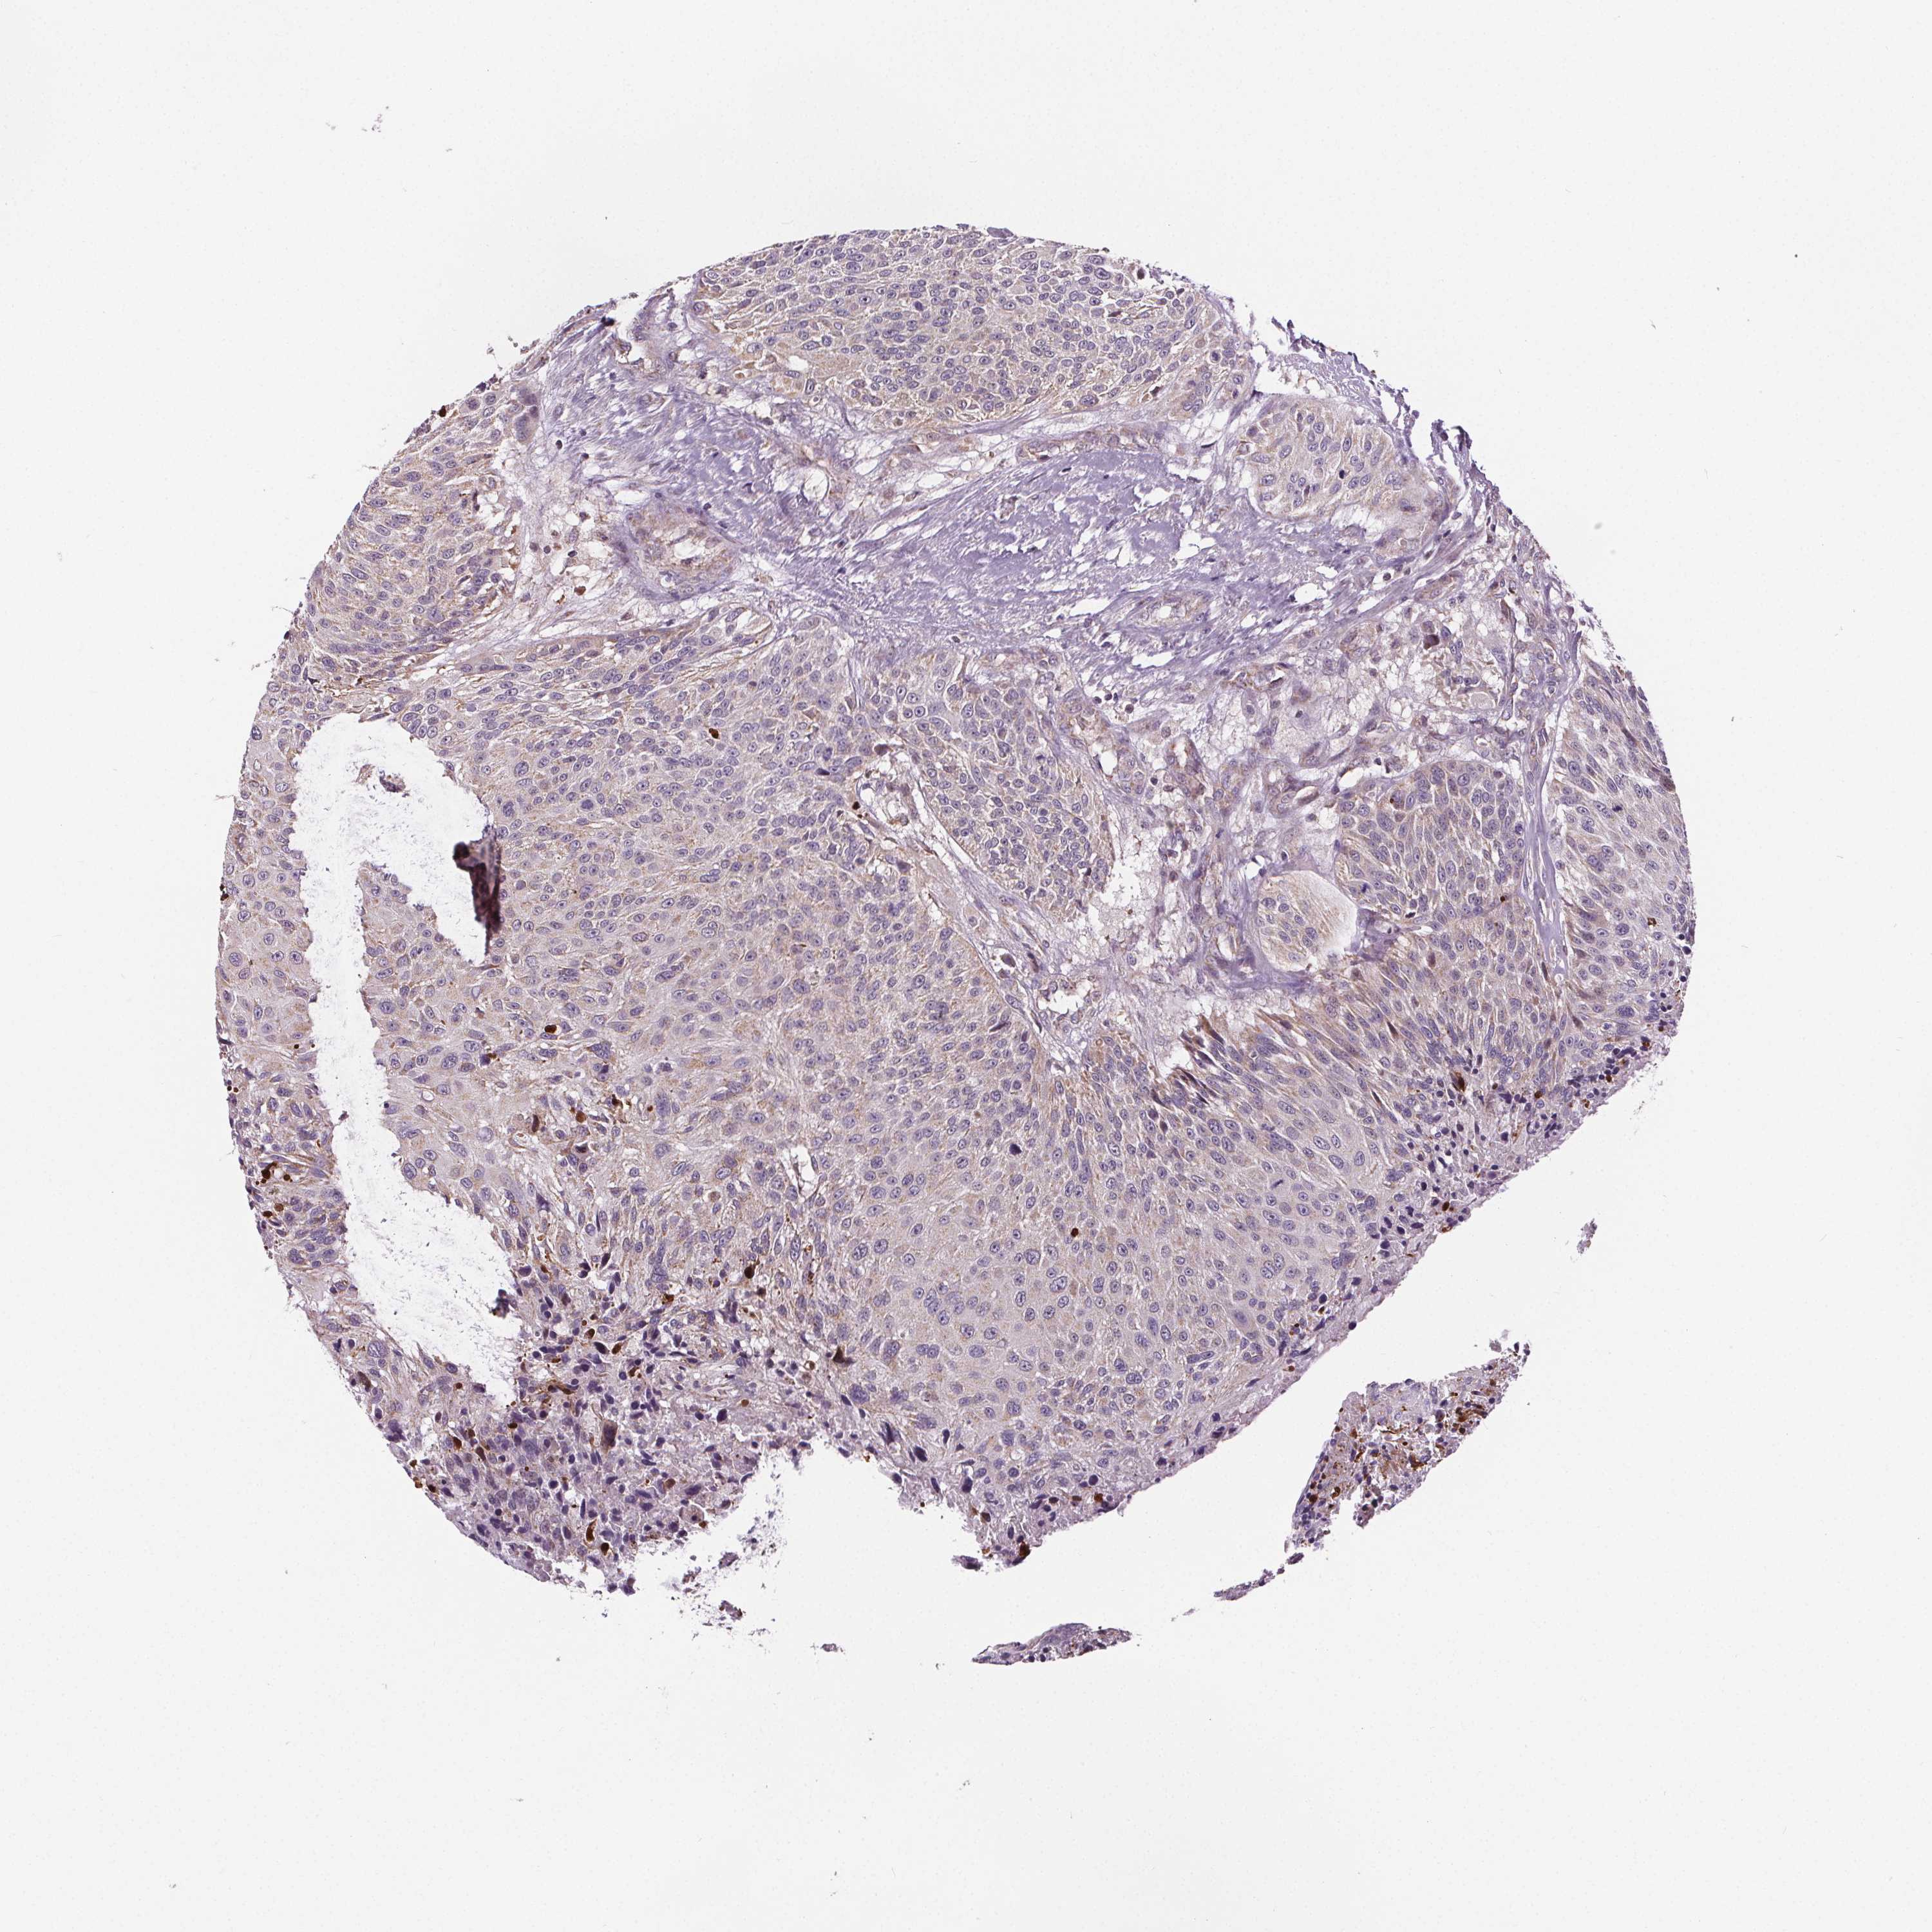

UROTHELIAL CANCER - Protein expressioni

A mouse-over function shows sample information and annotation data. Click on an image to view it in a full screen mode. Samples can be filtered based on level of antibody staining by selecting one or several of the following categories: high, medium, low and not detected. The assay and annotation is described here.

Note that samples used for immunohistochemistry by the Human Protein Atlas do not correspond to samples in the TCGA dataset.

Antibody stainingi

Antibody staining in the annotated cell types in the current human tissue is reported as not detected, low, medium, or high, based on conventional immunohistochemistry profiling in selected tissues. This score is based on the combination of the staining intensity and fraction of stained cells.

Each image is clickable and will lead to virtual microscopy that enables deeper exploration of all samples and also displays staining intensity scores, fraction scores and subcellular localization as well as patient and tissue information for each sample.

Antibody HPA039435

Antibody HPA039536

Antibody HPA061528

Urothelial carcinoma, High grade

Urothelial carcinoma, Low grade

Urothelial carcinoma, NOS